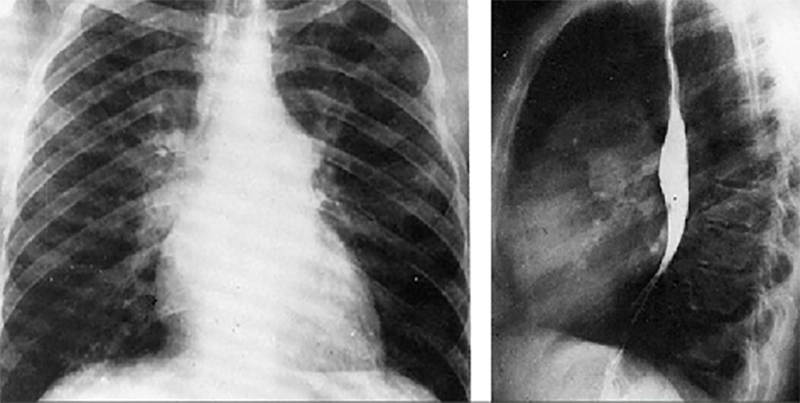

These chest X rays taken during a barium swallow show right ventricular enlargement, a large pulmonary trunk, pulmonary venous congestion and a left aortic arch.

The PA view demonstrates dilation of the pulmonary trunk manifested by the convex density below the aortic knob. Pulmonary venous congestion is suggested by prominent, fine vascular markings seen in the upper lung fields. The left aortic arch is indicated by deviation of the tracheal air shadow to the right and presence of the aortic knob at the upper left mediastinal border. In the lateral view, right ventricular enlargement is demonstrated by loss of the retrosternal air space.